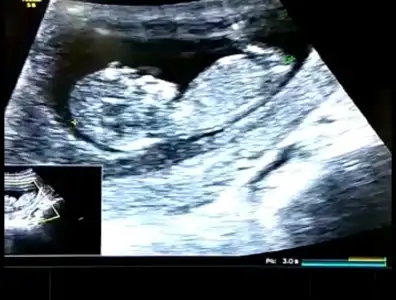

👫 11 yada 12 yada 13 hafta Nub usg nizi konumuza paylaşın

Arkadaşlar tahmin var mı? Özellikle ikra meyra :) Rabbim hayırlısını nasip etsin inşallah. 11+5

Evet oda kıza benzetti :) yanılma ihtimalimiz yüksek bu haftalarda ama kıza benzettim dedi! ama 3 hafta sonra falan gel artık şimdilik sıkı takibe gerek yok, hastalık falanda var diye.

İkimizde kız demişiz bencede kızdır 😍